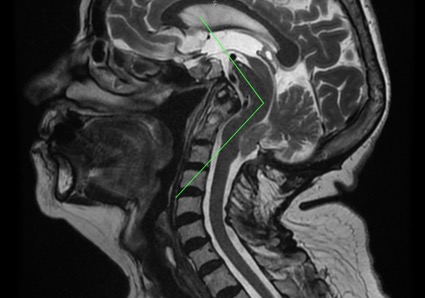

圖2 – 腦頸部磁共振片,影像可見齒狀突畸形、顱底凹陷、小腦扁桃體下疝及腦幹扭結症。另外,值得強調一提的是小腦上方明顯可見的空間,圖中驗證了終絲牽扯的理論並同時推翻後顱窩空間不足造成下疝的理論。

齒狀突畸形一般多是透過腦部或腦頸部CT掃描或是核磁共振進行診斷,透過Thiébaut線、Wackenheim線或Vrousos線進行測量。